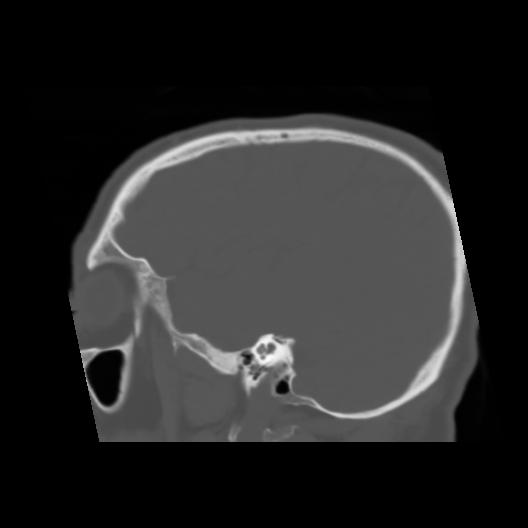

6 CEREBRO,,Sagittal,3.000,CEREBRO,Sagittal,